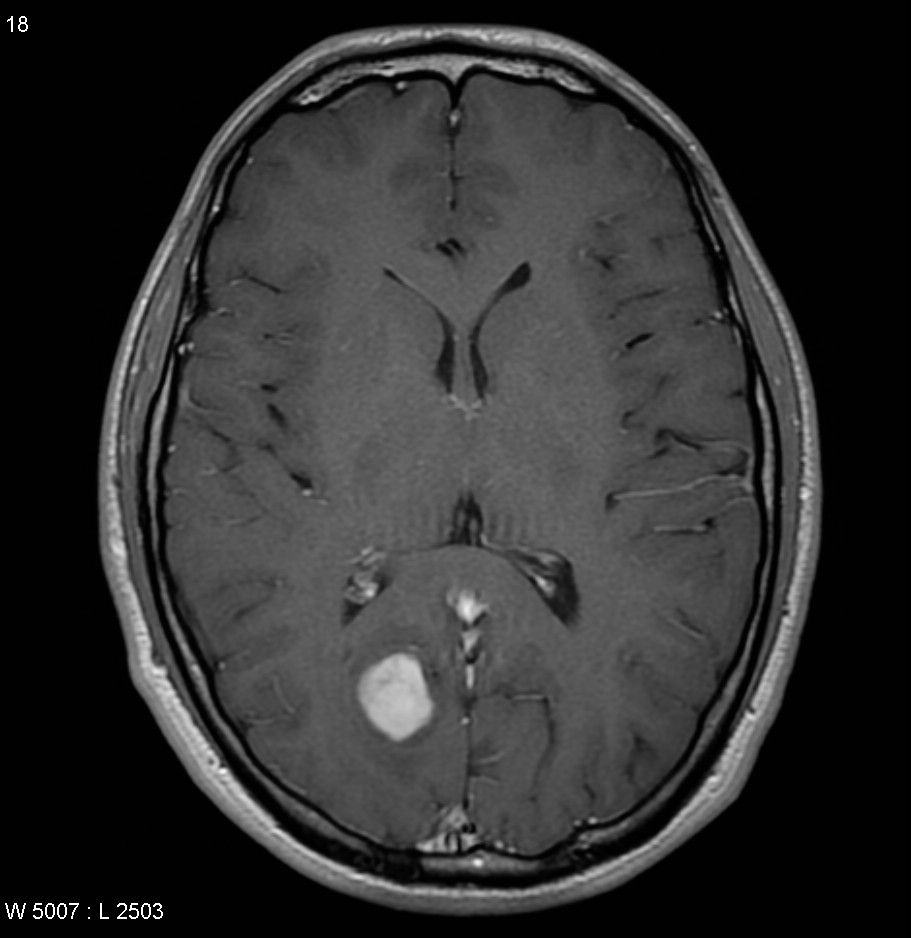

Patients with brain tumors may complain symptoms of headache, dizziness, vomiting, blurred vision, limbs weakness, etc.. Other symptoms include seizures and endocrine disorders; Personality or behavior changes may also occur. With modern advances in brain imaging technology, Computerized Tomography (CT) scan and magnetic resonance imaging (MRI) are the most commonly used diagnostic tools.

MRI does not involve radiation risk. Patients are required to lie inside the scanner with a strong magnetic field. Patients will not feel pain during the scanning process. MRI images can be achieved in a number of different angles and through a variety of different “signals”, so as to letting us to explore more about the tumors’ nature, thus allowing neurosurgeons making the most appropriate treatment plan for patients.